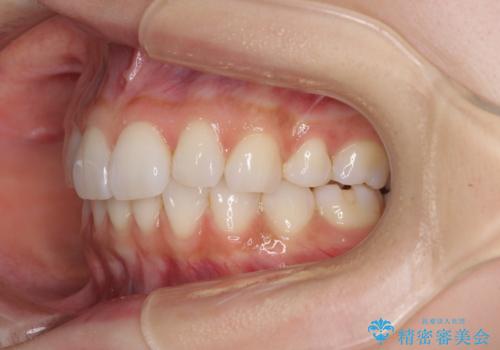

矯正治療の後戻り インビザラインによる再矯正治療

- 以前ワイヤー装置にて行った抜歯矯正の後戻りを気にして来院された患者様です。

前歯のデコボコにより、やや口元が突出した印象となっていたため、口元も引っ込めることとしました。

上下顎前歯に積極的にIPR(歯と歯の間を削る)を行い、インビザラインを用いて治療していくこととしました。

デコボコが解消されるのはもちろんのこと、突出感のあった前歯を引っ込めることができ、患者様には大変満足していただきました。